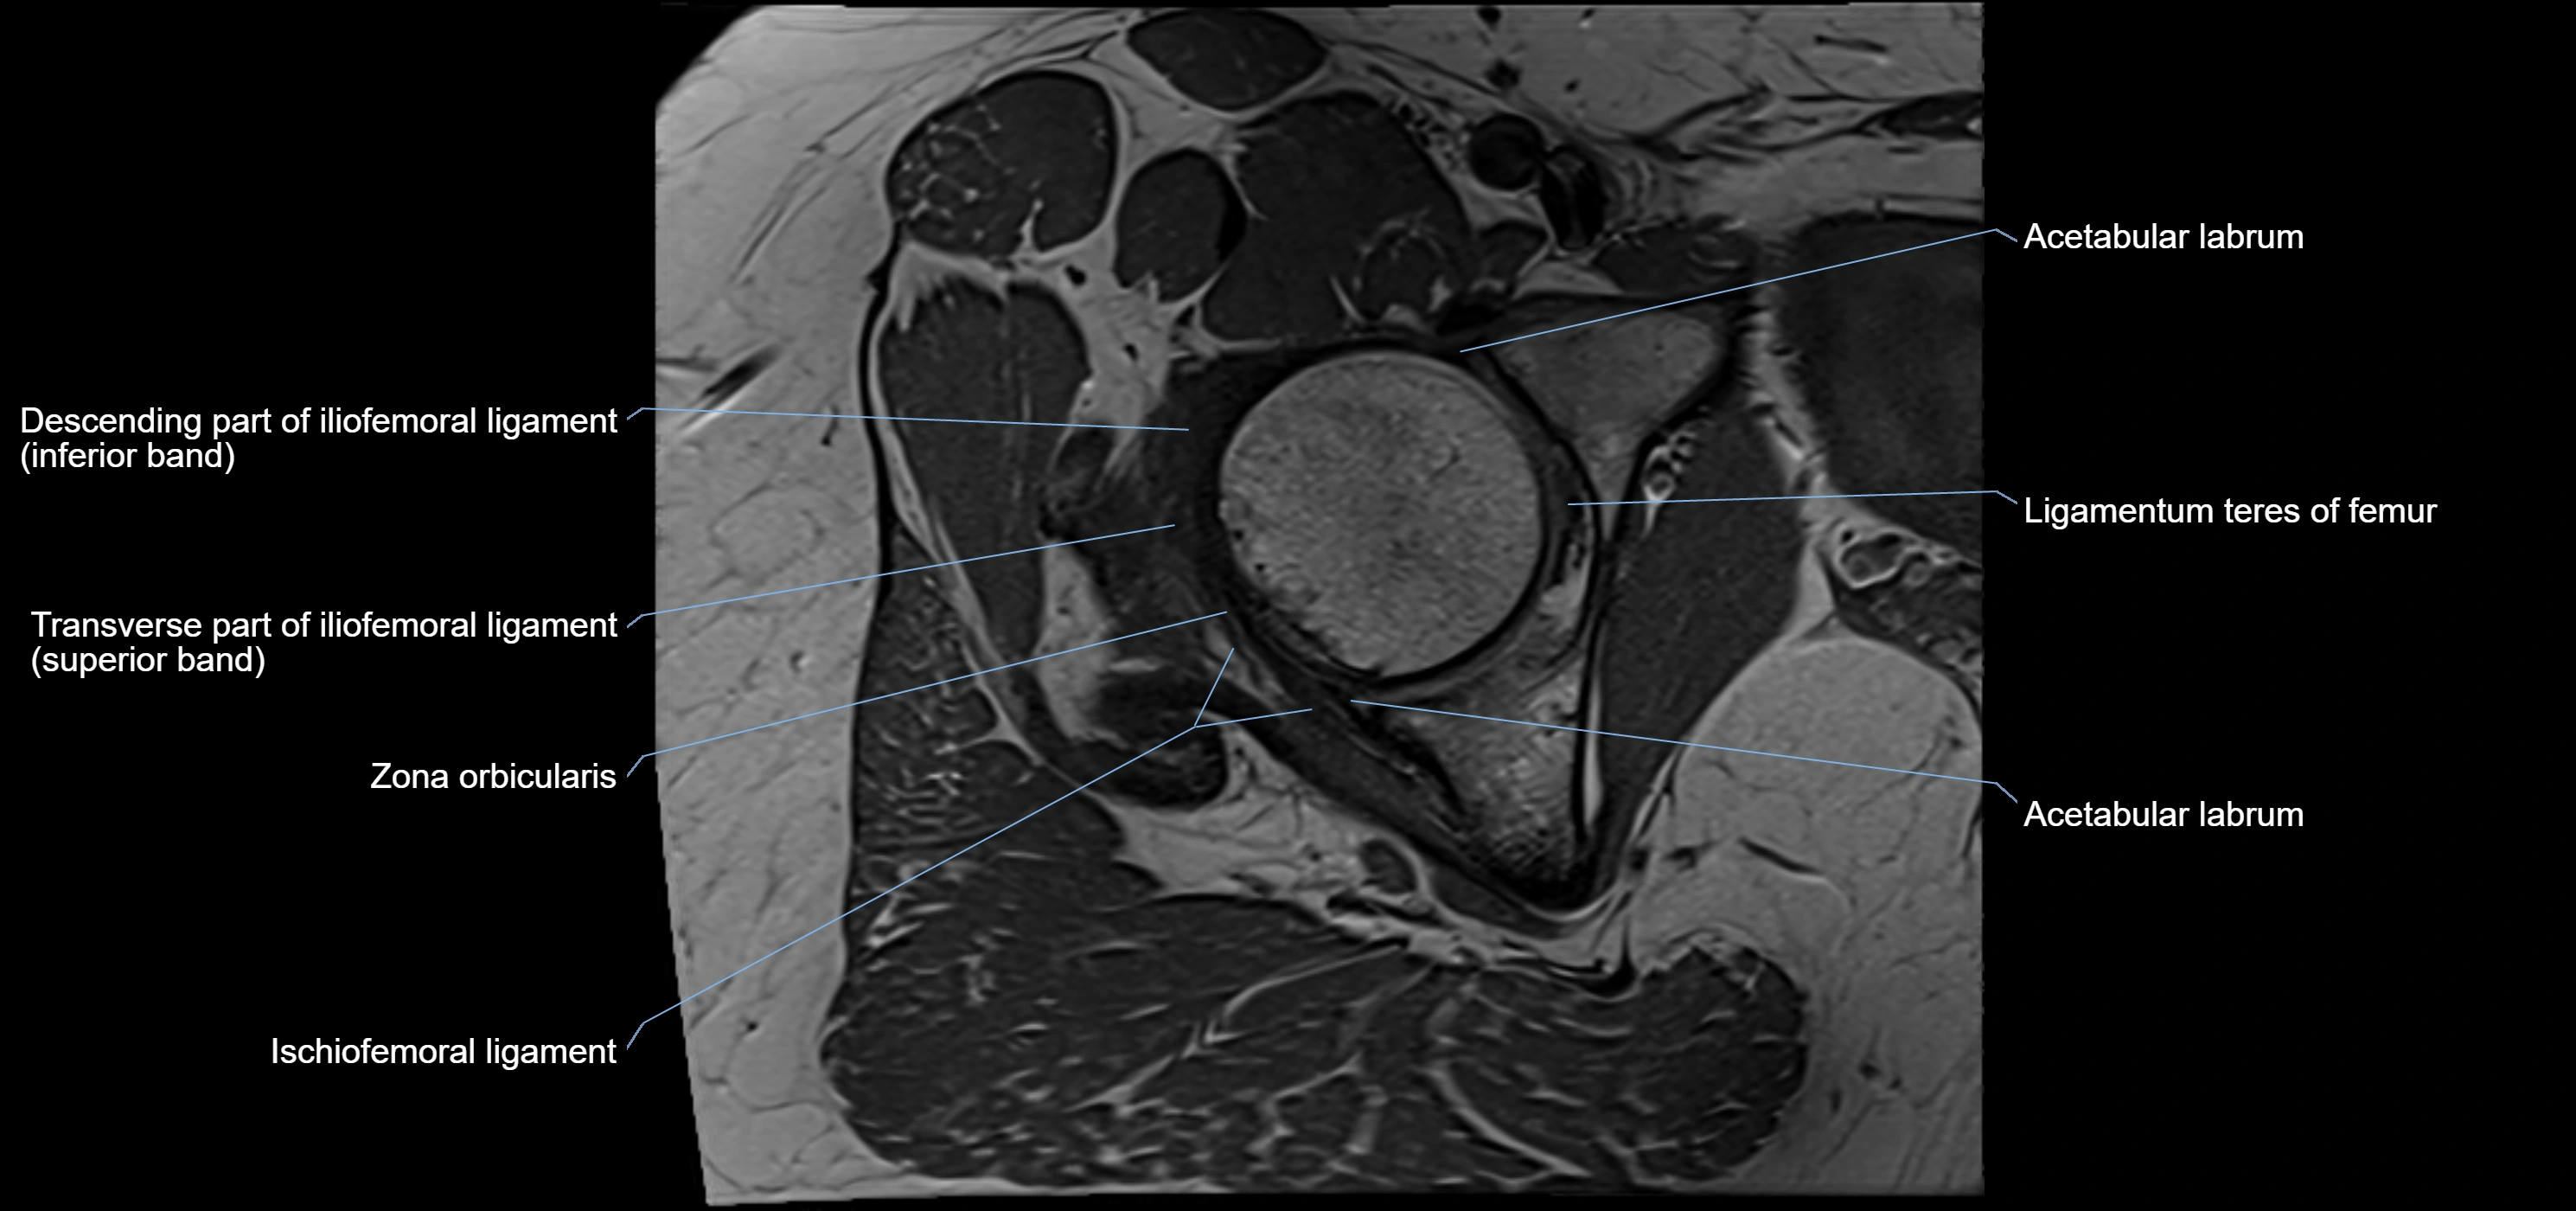

The acetabular labrum is a fibrocartilaginous ring that surrounds the rim of the acetabulum in the hip joint. It deepens the hip socket, increases joint stability, and maintains a suction seal that preserves negative intra-articular pressure. Structurally, the labrum transitions from hyaline cartilage of the acetabulum to dense fibrocartilage at its free edge.

It is triangular in cross-section, with its base attached to the acetabular rim and its apex projecting toward the femoral head. The labrum is most robust superiorly and anteriorly, where load bearing is greatest, and relatively thinner inferiorly.

Structure and Relations

• Superior and anterior labrum: thickest portions, stabilizing against anterior dislocation

• Inferior labrum: blends with the transverse acetabular ligament bridging the acetabular notch

MRI Appearance

T1-weighted images:

• Labrum: low signal intensity (dark)

• Surrounded by intermediate signal joint fluid (bright on arthrogram)

• Tears: linear or focal areas of intermediate-to-high signal interrupting labral continuity

T2-weighted images:

• Joint fluid: bright, making labral tears visible as fluid extending into or around labrum

• Degeneration: may show areas of increased signal within labrum

MRI image

image